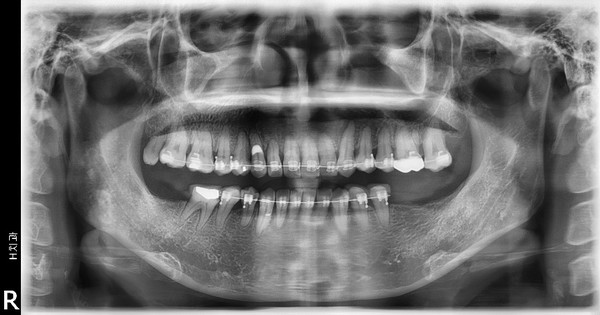

이 환자는 하악우측 제2대구치와 좌측 제1,2대구치가 결손된 환자로 하악 양측 distal cantilever 보철물 하방의 식편압입과 잇몸염증을 주소로 내원하였습니다. 또한 전치부의 crowding을 해결하기 위한 전악교정치료를 원하셨습니다.

하악구치의 cantilever 보철물을 제거하고 temporary crown으로 수복하여 bracket을 부착하였으며 결손부위는 일단 놔둔 상태에서 교정치료를 진행하였습니다.

전치부 decrowding의 영향을 고려하더라도 상하악 전치부의 flare와 동요도가 발생하였는데 이는 대구치부위 posterior support의 부재의 영향이 큽니다.

상악에서 miniscrew를 이용한 2mm 정도의 total arch distalization을 계획하였으므로 상응하는 최종교합형성을 고려하여 하악 대구치부에 임플란트식립을 진행하였고 구치부 support의 조기확립을 위해 temporary crown을 이용한 임플란트 상부보철 진행후 하악치열의 후방이동을 진행하기로 하였습니다.

하악임플란트상부보철물에 tube를 부착하되 tube slot에 각형호선이 가급적 passive 하게 들어가도록 보철물의 모양과 tube 부착위치를 조절하였습니다. 계획된 후방이동량만큼 임플란트 보철물과 전방 자연치간의 space를 형성하여 전방치열을 후방견인하였습니다.

마무리된 교합은 초진시에 동일하게 양측 Class 1 교합으로 마무리하였으며 측모두 부방사선 사진에서 보듯 교정중 발생했던 전치의 flare가 개선되었습니다.